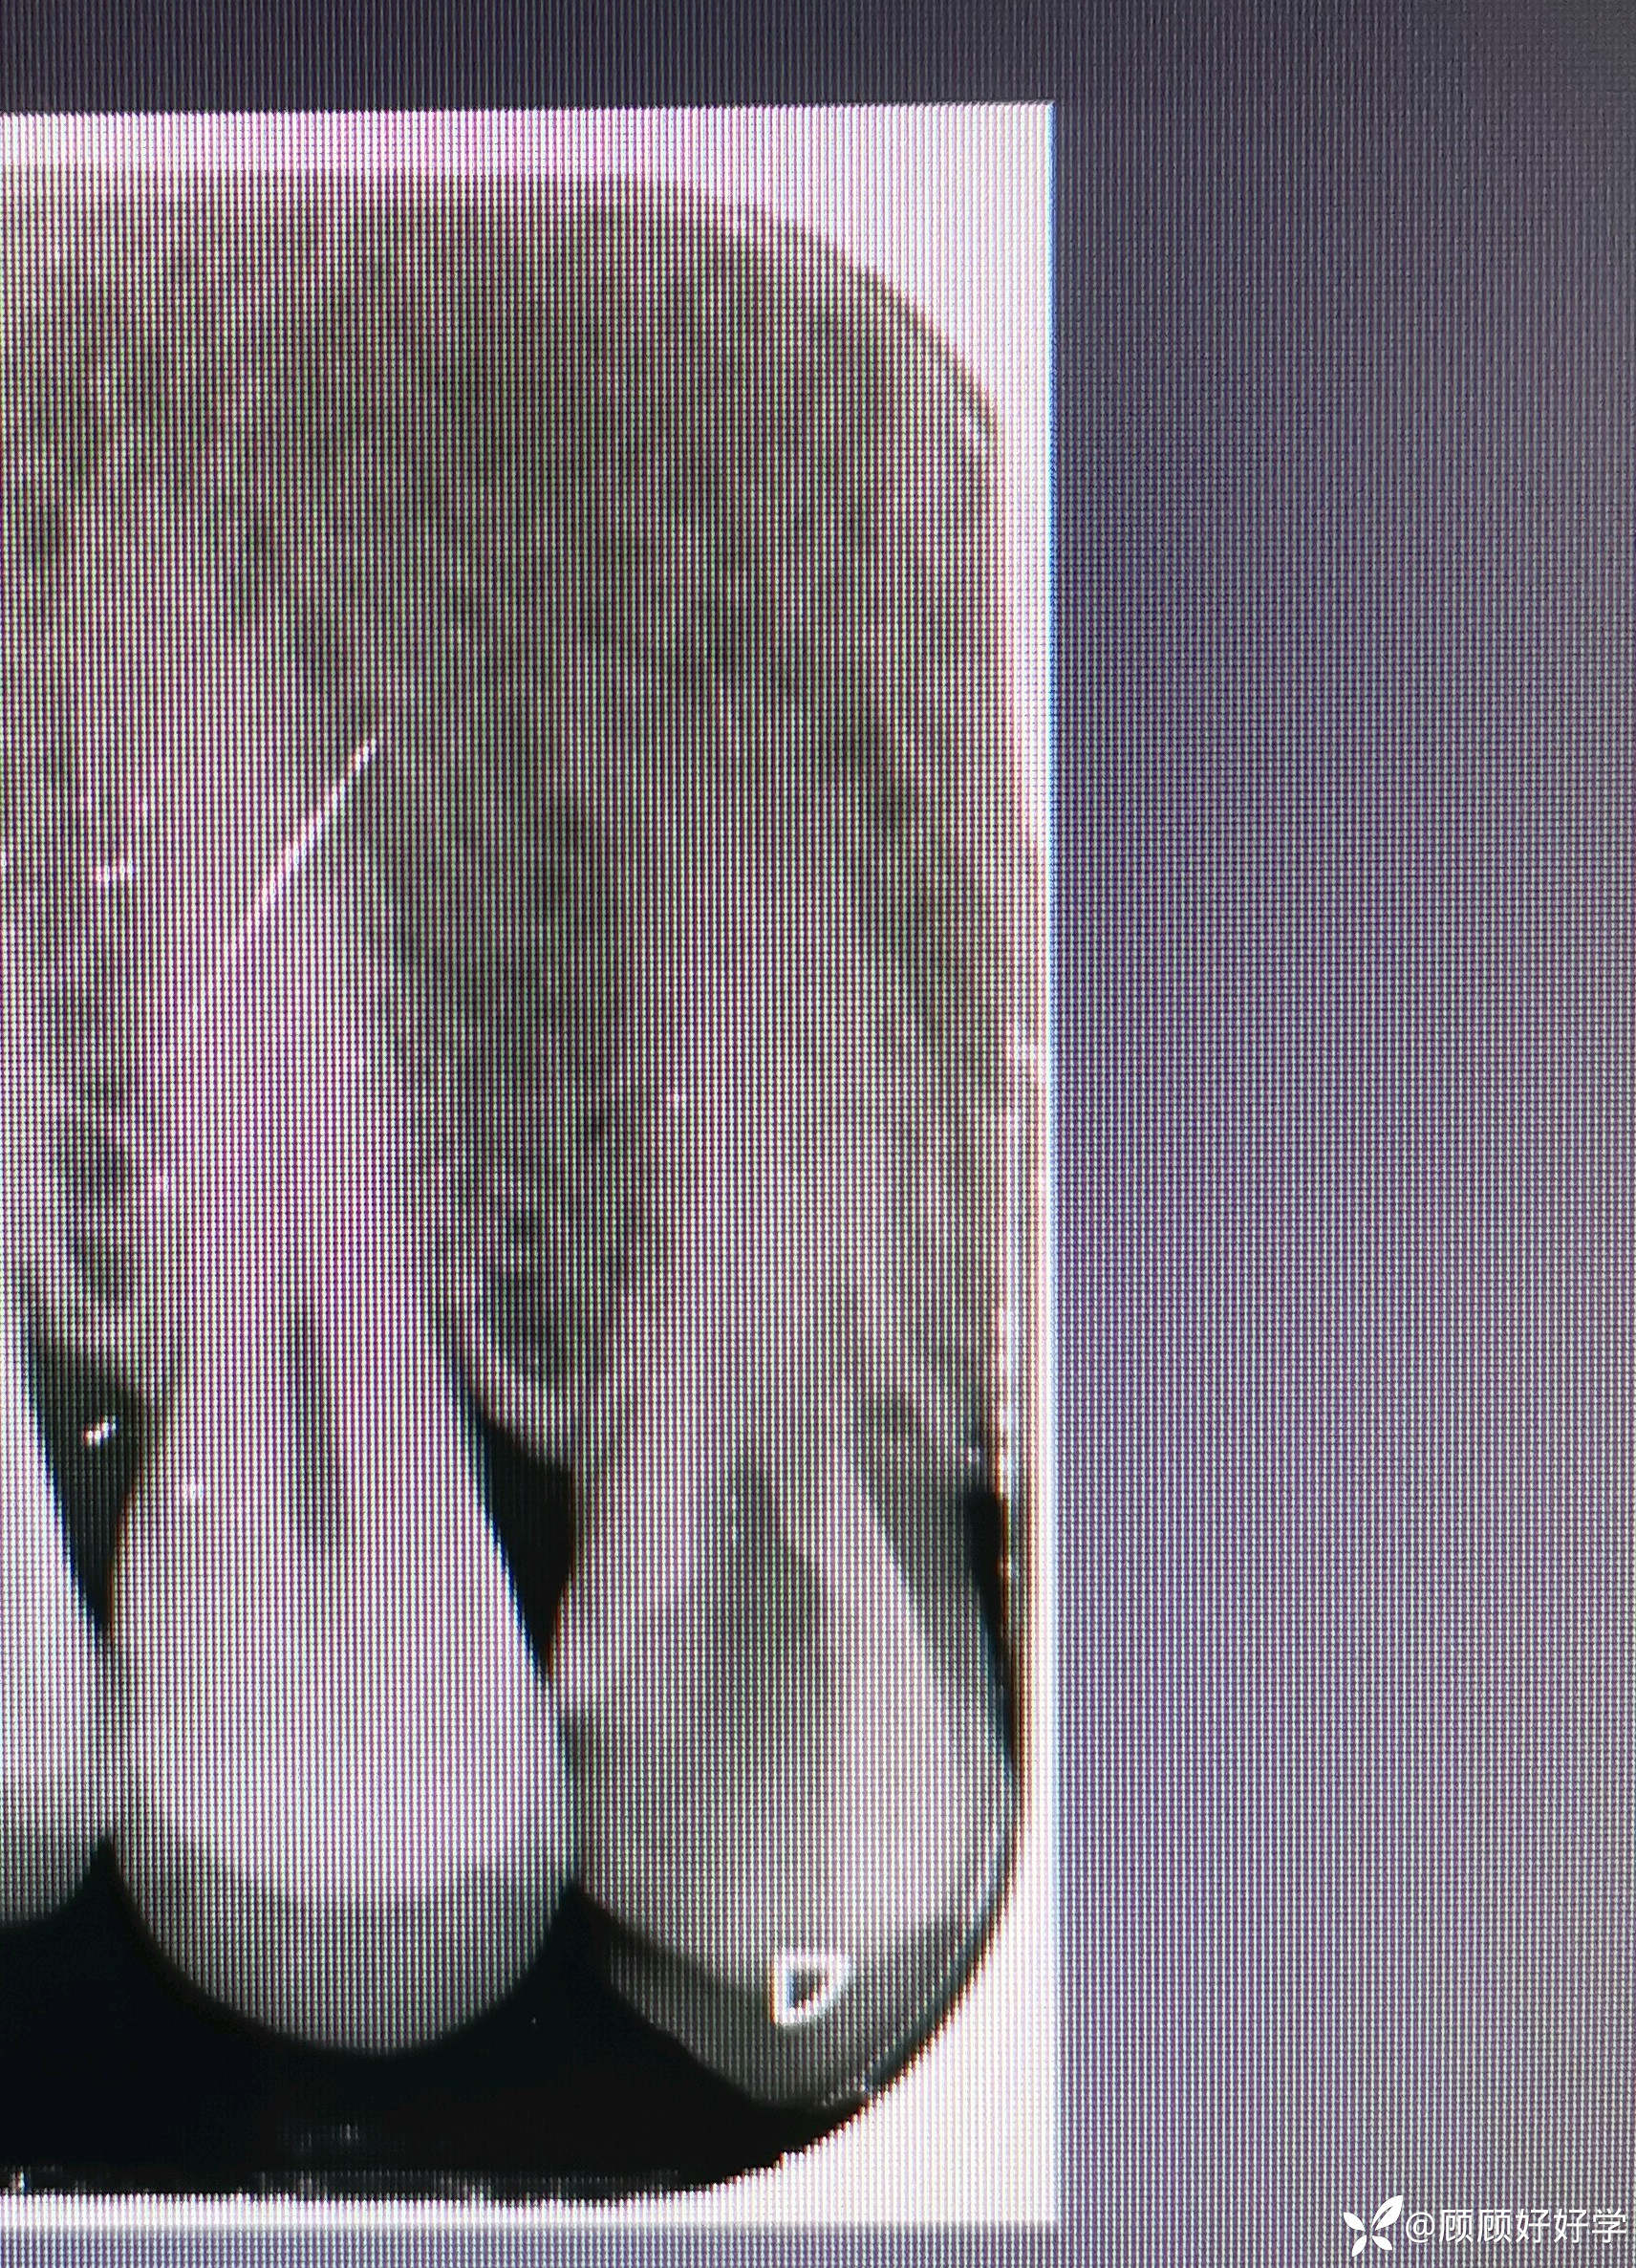

08号K锉进入颊根确定旁路,根测仪可至0.4,更换10号K锉、C型锉、15号H锉疏通均至0.2左右,测得数据22mm,机扩畅通锉反转,止动片21mm左右,期间生理盐水超声荡洗交替进行。再使用10K锉根测时可至0.0,且手感自觉根管内畅通,插诊拍摄根尖片检查如下

此时才发现将分离机械推出根尖孔